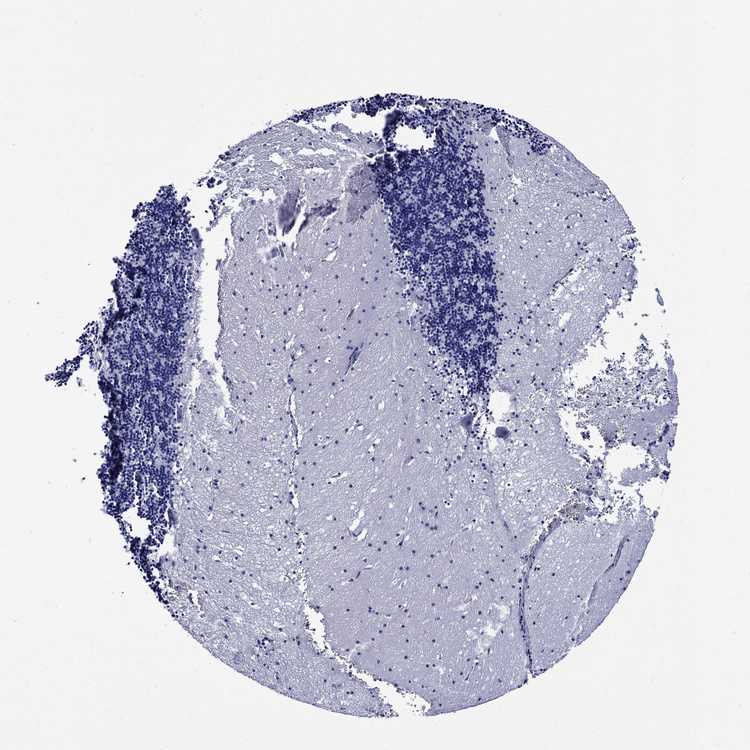

CEREBELLUM - Antibody stainingi

Antibody staining in the annotated cell types in the current human tissue is reported as not detected, low, medium, or high, based on conventional immunohistochemistry profiling in selected tissues. This score is based on the combination of the staining intensity and fraction of stained cells.

Each image is clickable and will lead to virtual microscopy that enables deeper exploration of all samples and also displays staining intensity scores, fraction scores and subcellular localization as well as patient and tissue information for each sample.

Antibody HPA059558

Purkinje cells Not detected

Cells in granular layer Not detected

Cells in molecular layer Not detected